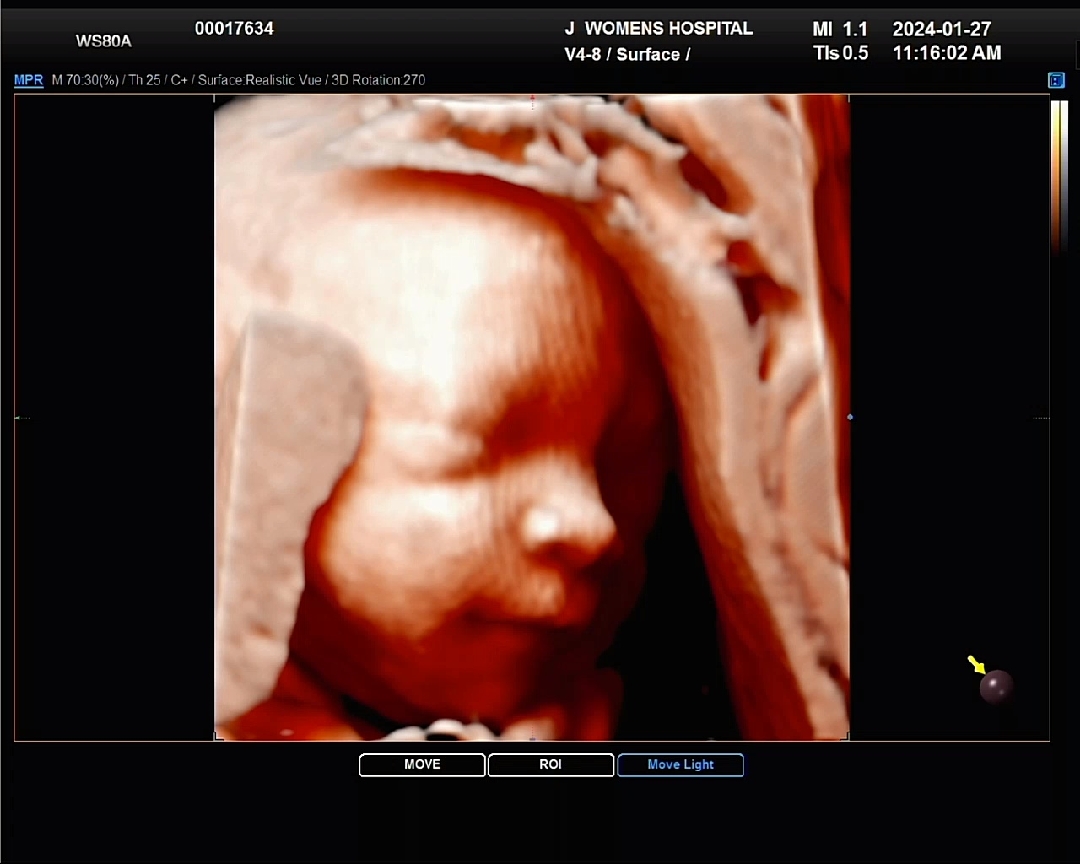

약간 미소지어줬다고 병원에서 엄청 좋아하더라구요 ㅋㅋㅋ 저번에 하도 움직여서 발가락 갯수도 못셌는데 이번엔 임당검사 하느라 2시간 금식 했더니 적당히 움직여줬네요! 딸인데 아빠 닮아보여서 기대되네요 ㅎㅎ

와우 교과서처럼? 나왔어요 화질도 진짜 좋네요

코가 진짜 너무 예쁘네요.. 윳는 모습도 넘 예쁘구요!!!